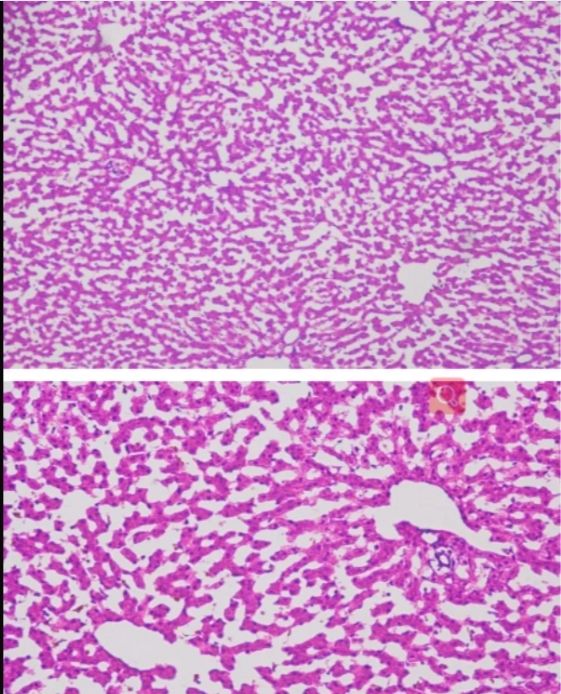

今天普拉特澤生物繼續(xù)跟大家一起學(xué)習(xí)新的實驗——冰凍切片,是一種重要的實驗技術(shù),它在低溫條件下使組織快速冷卻到一定硬度,然后進行切片。這種技術(shù)具有簡便、快速、組織變化小以及能夠保存脂肪和類脂等成分的優(yōu)點,被廣泛應(yīng)用于生物學(xué)、醫(yī)學(xué)等領(lǐng)域。本文將詳細介紹冰凍切片實驗的原理以及其在各個領(lǐng)域的應(yīng)用。 冰凍切片實驗原理以及應(yīng)用由普拉特澤生物組織染色檢測平臺總結(jié)分享,組織染色檢測平臺為廣大科研實驗人員提供冰凍切片外包實驗服務(wù),先一起來學(xué)習(xí)學(xué)習(xí)什么是冰凍切片~

冰凍切片實驗的原理基于低溫下組織的物理性質(zhì)變化。在冷凍狀態(tài)下,組織內(nèi)的水分形成冰晶,使組織變得堅硬而易于切片。這種切片方法不需要對組織進行固定、脫水、透明、包埋等繁瑣步驟,因此大大縮短了制片時間。同時,由于避免了化學(xué)處理或加熱過程,冰凍切片能更好地保存組織的原始結(jié)構(gòu)和成分,特別是對于那些對有機溶劑或熱敏感的細胞表面抗原和水解酶。

冰凍切片在病理學(xué)診斷中具有重要應(yīng)用價值。通過冰凍切片技術(shù),病理醫(yī)生可以快速獲取組織樣本的切片,進行顯微鏡下觀察和分析。這有助于醫(yī)生在術(shù)中快速判斷腫瘤的性質(zhì)、淋巴結(jié)是否有轉(zhuǎn)移等關(guān)鍵信息,從而指導(dǎo)手術(shù)范圍和后續(xù)治療方案。

冰凍切片還可以用于免疫組化研究。通過冰凍切片技術(shù),研究人員可以制備含有特定抗原的組織切片,進而利用免疫組化方法檢測和分析抗原的表達情況。這對于研究細胞的生物學(xué)功能、疾病的發(fā)生機制以及藥物的療效評價具有重要意義。